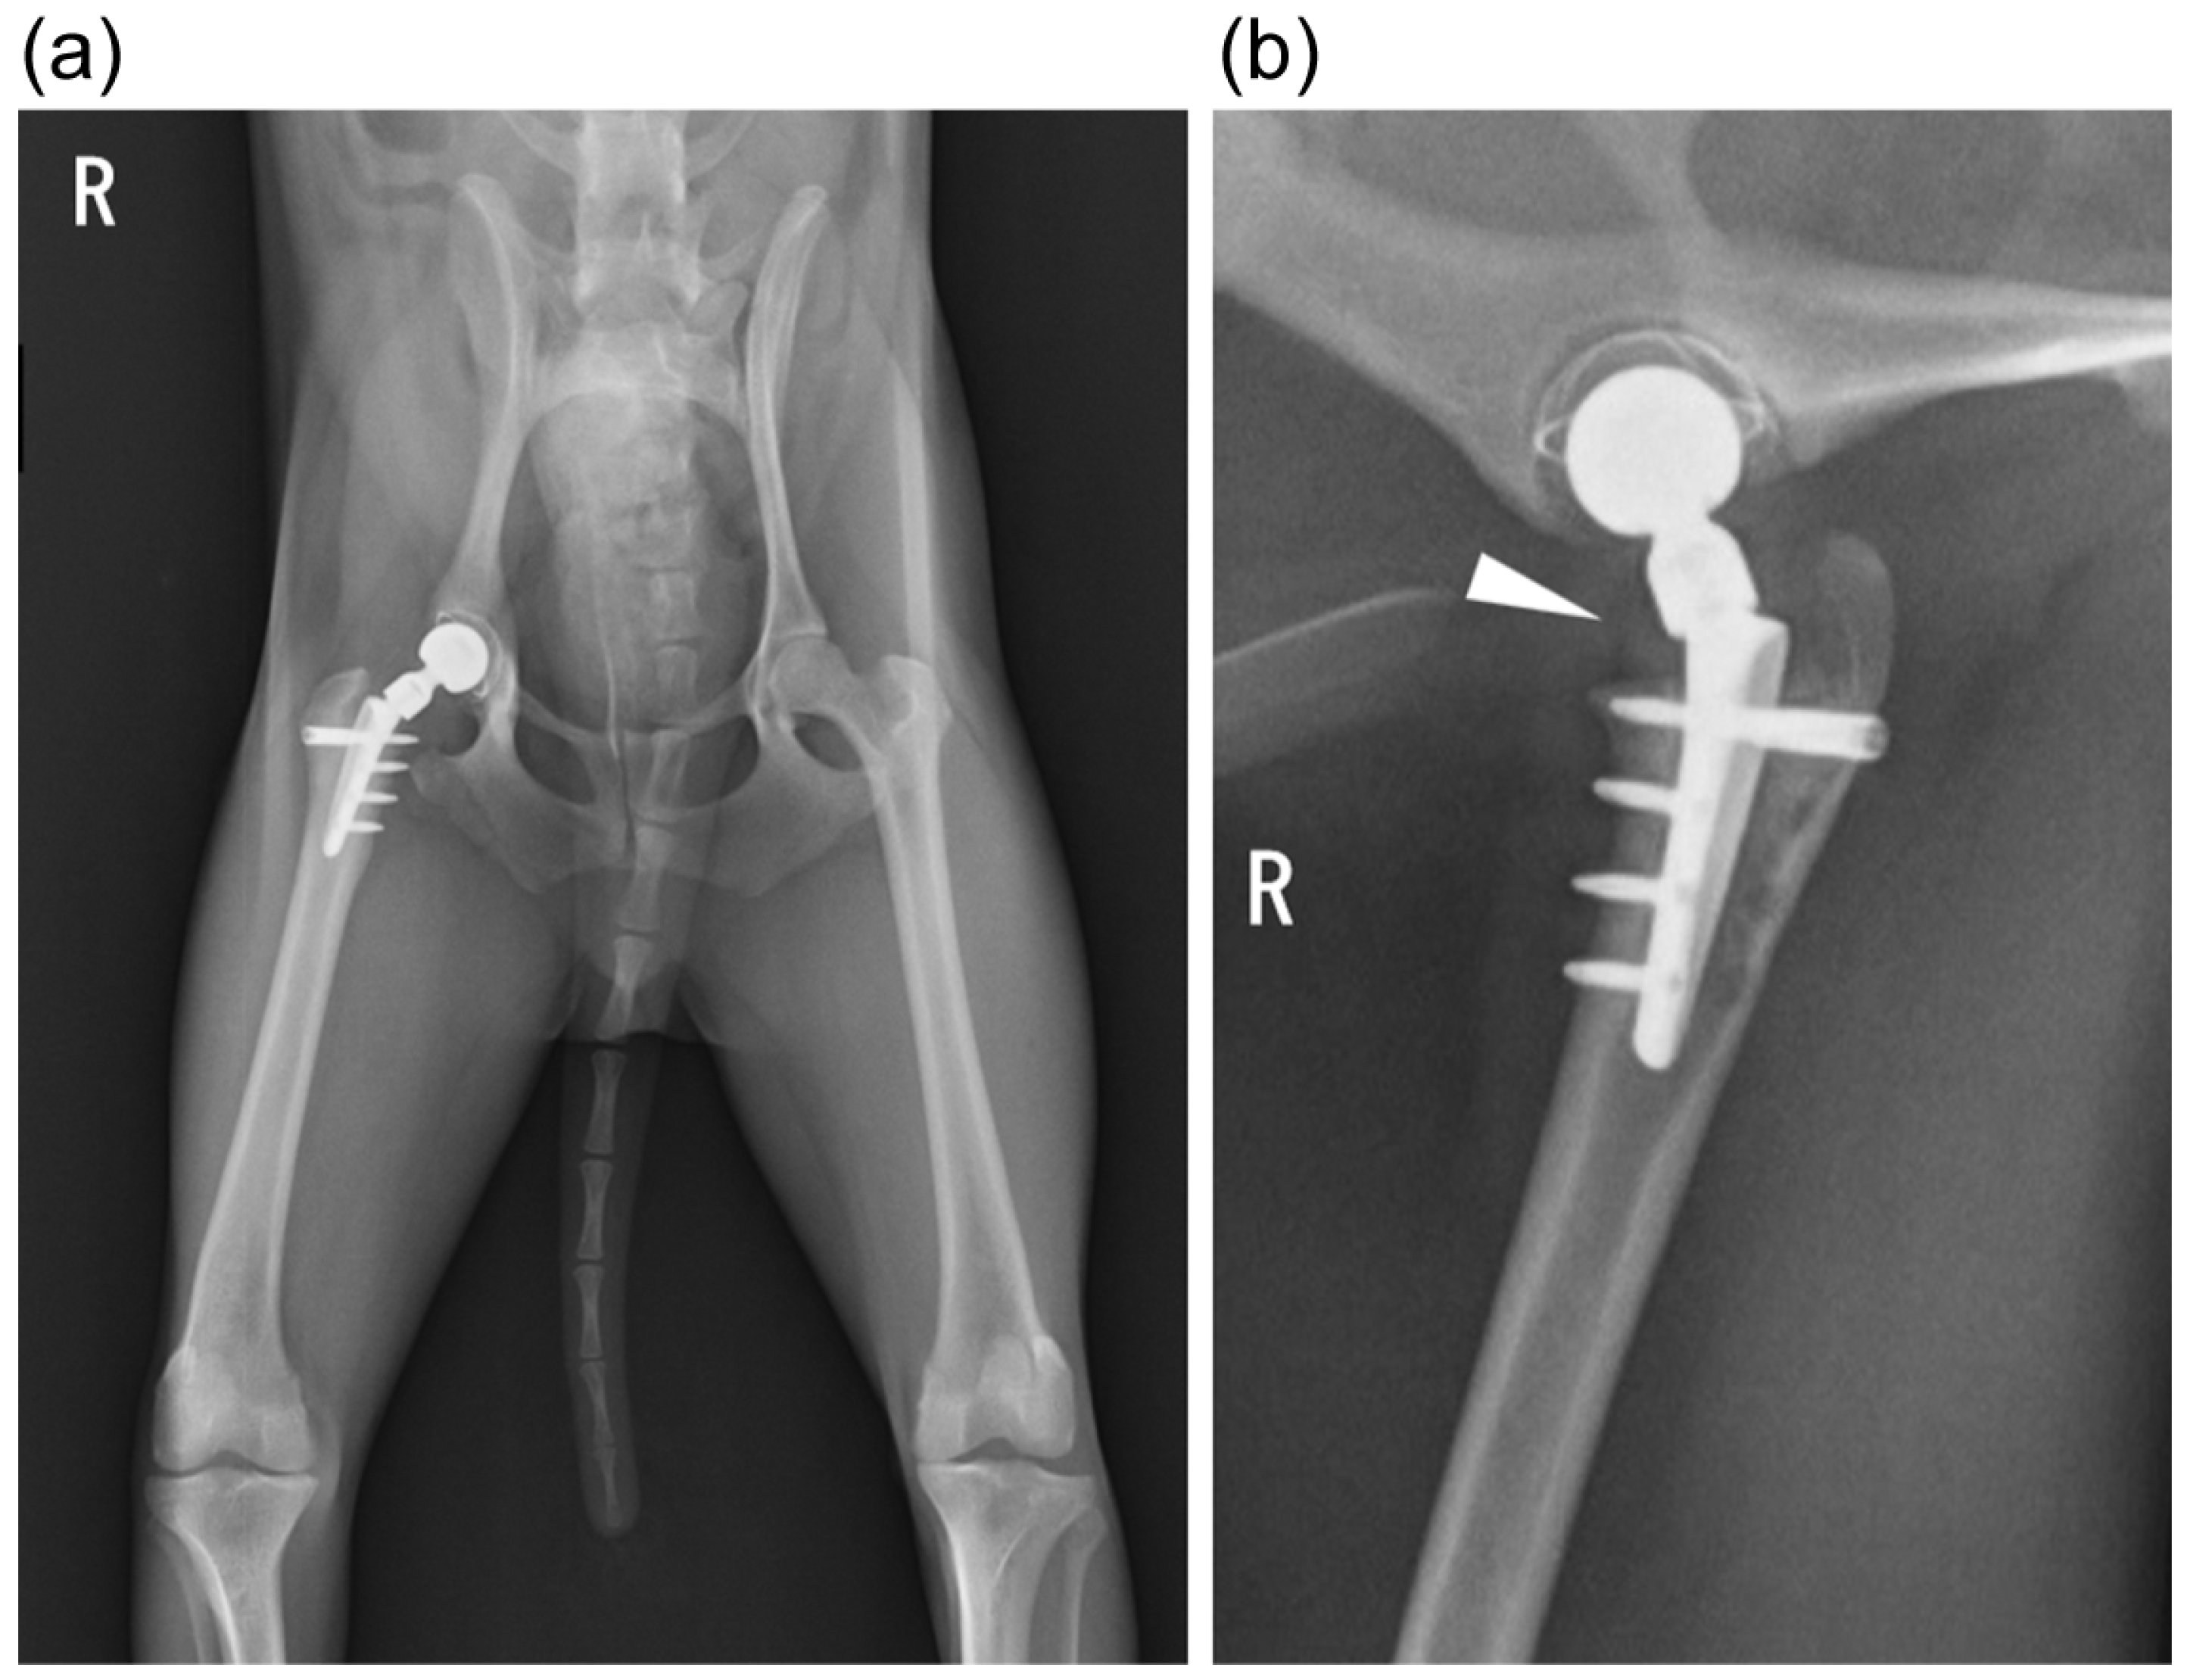

Figure 1.

Postoperative radiographs after first total hip replacement surgery (right hip). (a) Ventrodorsal view; (b) yoga view: the stem was placed slightly proximally, as indicated by the arrowhead.